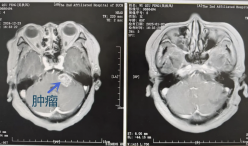

陕西中医药大学第二附属医院:精湛医术丨听力减退 警惕脑肿瘤作梗!

65岁的吴大妈,2年前出现左侧听力减退,误以为是年龄引起的听力退行性退,没及时检查治疗。半年前,她突然左侧面部、舌尖麻木,感觉和味觉也出现减退,吃了中药还是不见好。最近,大妈好端端地又出现头晕、恶心呕吐的症状,耳根周围还疼痛不已。在当地医院检查后发现,大妈患上的叫听神经瘤!